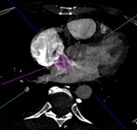

В статье представлен случай успешного хирургического лечения тромбоэмболии легочной артерии у пациентки с высоким риском ранней сердечной смерти на фоне парадоксальной эмболии, осложненной острым нарушением мозгового кровообращения. Криптогенное острое нарушение мозгового кровообращения в комбинации с тяжелой прогрессирующей правожелудочковой недостаточностью на фоне ТЭЛА обусловливает серьезные трудности при принятии решения в отношении тактики лечения у данных больных. Внутрисердечная локализация тромбоэмбола, угрожаемая развитием не только рецидива тромбоэмболии легочной артерии, но и парадоксальной эмболии требует незамедлительного выполнения комплекса дифференциально-диагностического обследования, направленного на верификацию патофизиологического механизма развития заболевания, что во многом определяет эффективность проводимого лечения. Анализ доступных литературных данных, приведенный в работе, а также анализ клинического случая позволяют выработать тактический алгоритм в этой группе пациентов и определить показания к открытому оперативному вмешательству.